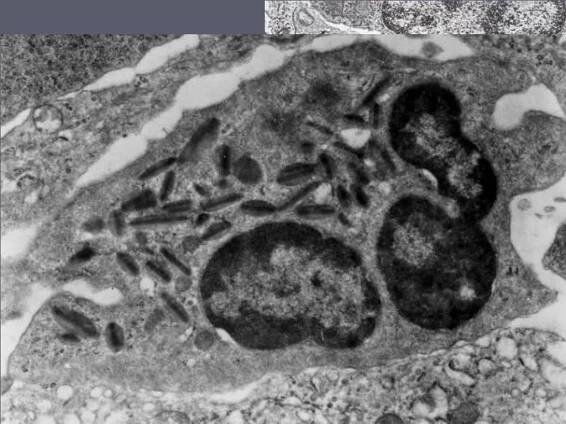

Eosinofilní granulocyty, nebo také eozinofily, jsou buňky imunitního systému patřící do skupiny granulocytů. Mají charakteristickou morfologii, kdy jsou v cytoplasmě patrné četné granule a velké dvoulaločnaté jádro [1 ]. Název získaly podle…

Eozinofilní granulocyty (eozinofily) jsou bílé krvinky, které se řadí mezi granulocyty (společně s neutrofily abazofily).

Eozinofily jsou podtypem leukocytů (přesněji řečeno patří mezi granulocyty). Za normálních v krevním obraze tvoří pouze 1-3% bílých krvinek. Eozinofily vznikají v kostní dřeni a následně se dostávají do krve a jednotlivých tkání.